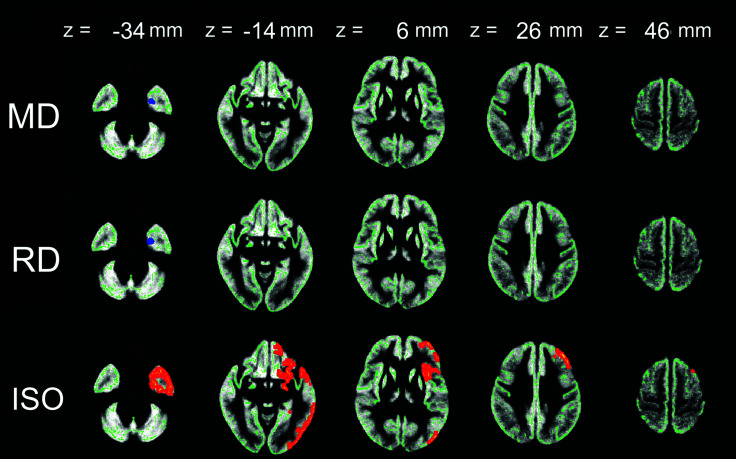

Results: TBSS analysis showed that patients with BMS had significantly higher FA and ICVF and lower MD and RD than the healthy control subjects (family-wise error [FWE] corrected P < 0.05). Changes in ICVF, MD, and RD were observed in widespread white matter areas. Fairly small areas with different FA were included. GBSS analysis showed that patients with BMS had significantly higher ISO and lower MD and RD than the healthy control subjects (FWE-corrected P < 0.05), mainly limited to the amygdala.

Abstract Image